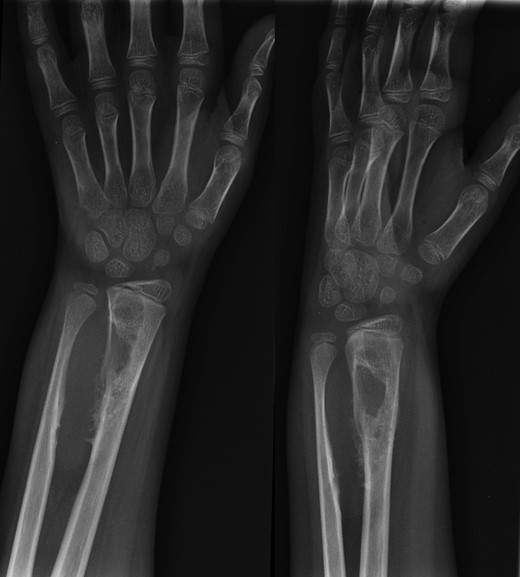

A 10-year-old male was referred to our office after being seen by a pediatric orthopedic surgeon for a distal left forearm mass with block in pronation and supination. The patient's past medical history is significant for a distal radius fracture 2 years prior to his aforementioned office visit. Follow-up radiographs after fracture union at that time showed no evidence of disease (Fig. 1). Radiographs taken at the time of presentation 2 years after fracture healing revealed a 6.5 cm long lesion in the distal syndesmosis arising from the radius. The lesion resulted in pressure erosions upon the distal radius and ulna, causing a slight splaying of the bones (Fig. 2).

AP and lateral radiographs of the left forearm showing 6.5 cm long lesion in the region of the distal syndesmosis between the radius and ulna.